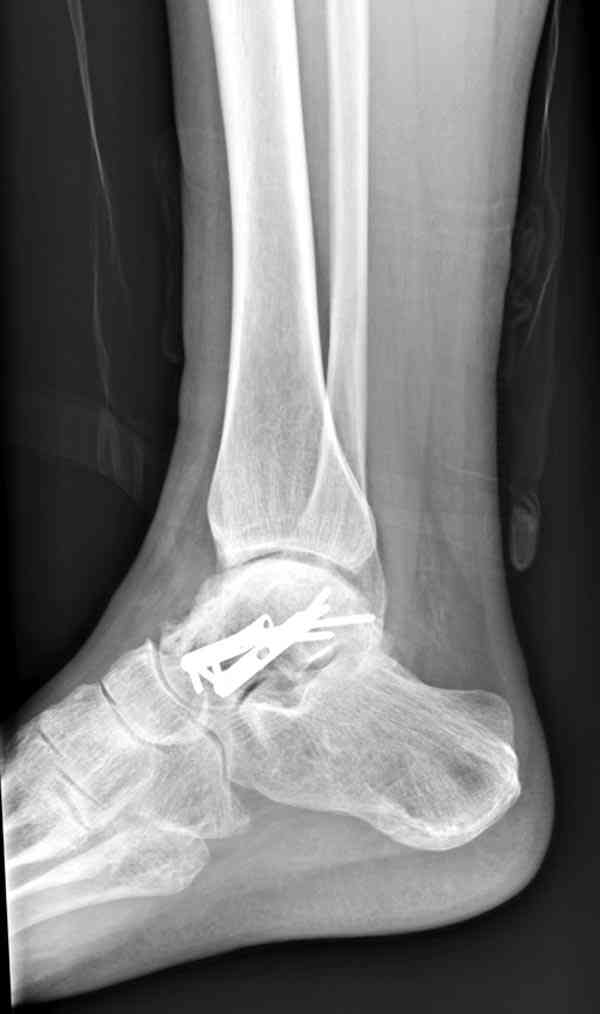

а основании двух видов ренгенограмм невозможно радикально решить о необходимости открытой репозиции или первичного артродеза.

Для оценки состояния нужны дополнительные исследования, например Canale или Broden ренгенограммы и Компьютерная томография.

При переломах тарана всегда имеется риск AVN, а классификация Hawkins поможет разобраться с предполагаемыми осложнениями.

Если в первом типе, когда перелом шейки без смещения, тогда AVN менее 10%, при втором типе когда имеется смещение и вывих тарана в субталарном сочленении меньше 40%, а при типе III когда смещение в голеностопном и субталарном суставах - около 90% и в типе IV, когда происходит полный вывих, риск AVN достигает 100%.

Для оценки состояния нужны дополнительные исследования, например

> Canale или Broden ренгенограммы

повторили рентгенограммы и доделали проекции, к единому мнению все еще не пришли